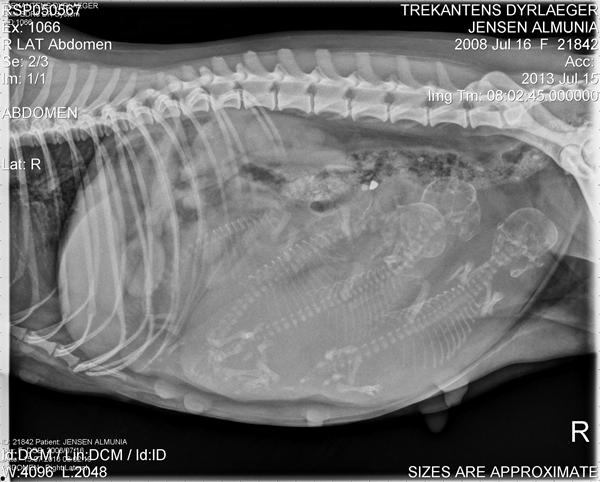

I mandags blev Almunia røntgenfotograferet, hun var på dag 58 fra første parring.

Jeg kan godt forstå at mange synes de kan se 5 hvalpe, men det snyder; der er altså "kun" 4 vapsere.

Jeg ser det så som at grøn og blå skal bytte kranier ud fra din tegning.

Forestil dig at blå rygrad ligesom krummer og ligger med øjnene nedad imod midten af maven, hvis det giver mening?

Og det er der jeg ser de fire.

Så ser også kun fire rygrader og fire kranier.